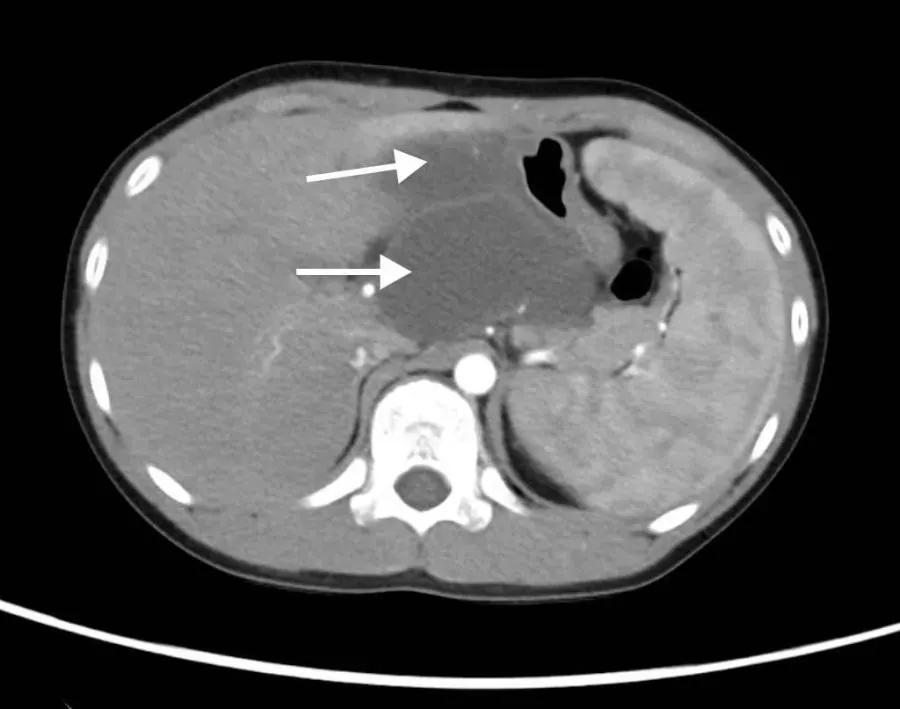

患儿胃部肿瘤的影像图

手术由普通外科闫军副主任医师和石永奎主治医师、宋二处住院医师共同完成。术中,医生发现与术前预判一致,但挑战远超预期:患儿腹腔空间狭小,病变位于胃体小弯侧网膜囊内关键区域,肿瘤直径11厘米,与肝脏、胰腺、横结肠系膜、小网膜、大网膜和后腹膜形成严重的包裹性粘连。加之病变为多囊性、质地脆弱,解剖结构异常复杂,手术分离中操作稍有不慎即可能损伤重要脏器或引发腹腔大出血。尽管手术难度增大,但在麻醉手术科和手术室护理团队的密切配合下,手术小组凭借丰富经验,耐心细致地一点一点剥离肿瘤,最终成功松解所有致密粘连,完整切除了胃部肿瘤组织,并确保术中肿瘤未破裂,最大程度降低了感染扩散风险,避免重要脏器损伤,完整保留了贲门功能。术中病理报告证实切缘阴性,标志肿瘤被彻底清除。